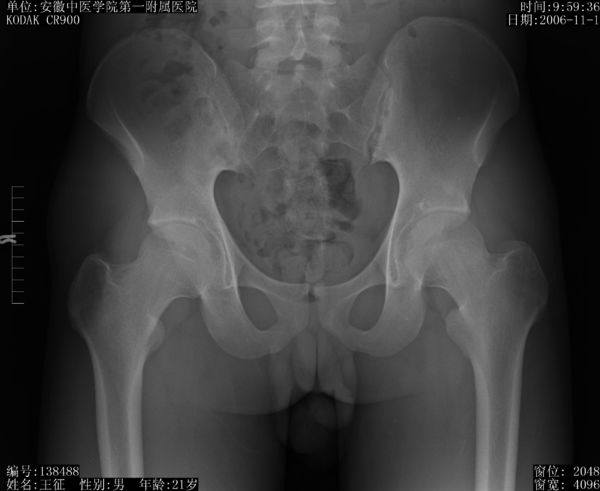

强直性脊柱炎也可以出现髋关节疼痛、跛行、活动受限。

图 强直性脊柱炎X线表现

举例:1例年轻患者在院外多家医院诊断的“股骨头坏死”准备做人工全髋关节置换手术,经介绍找到安徽省中医院

周章武医生,经检查确诊为强直性脊柱炎(图片及化验结果附后)。

如果对这么年轻患者盲目做了全髋关节置换手术,无疑是雪上加霜! 可能在手术后短时间内髋关节疼痛能缓解,但作为全身性病变的强直性脊柱炎没有治疗,它还会损害其它关节,会出现更多的关节损害!何况对这么年轻病做做关节置换手术还存在将来翻修等问题。希望广大医生和患者都要引起足够重视!

强直性脊柱炎多数影响到脊柱,侵犯髋关节和膝关节的病例也不少,强直性脊柱炎影响的髋关节病变最容易造成误诊,甚至误治,酿成严重后果!